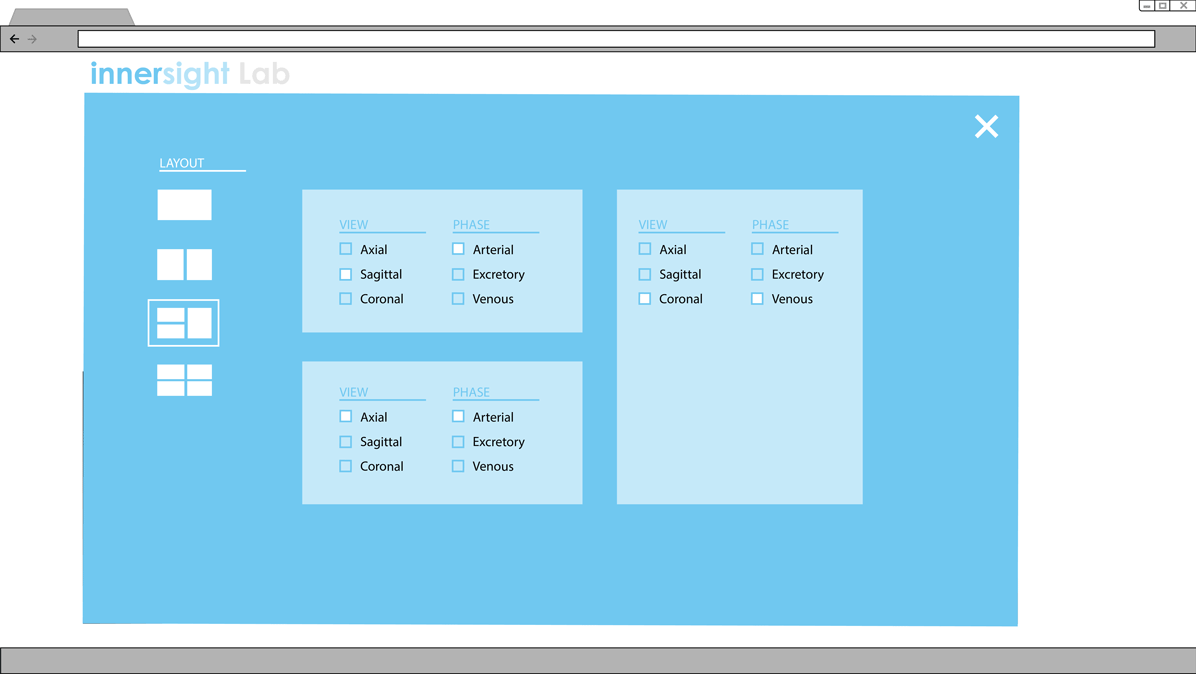

Proposal for Multi-View layout

Version 1

Control what's shown by clicking and unclicking boxes.

Clicking the 'Change layout' button opens up this menu.